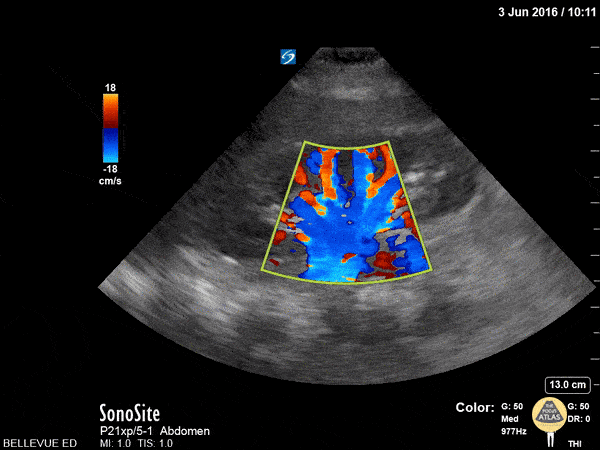

This clip shows a kidney with color doppler overlay. Using color doppler is helpful in distinguishing hydronephrosis from prominent renal vasculature which can look similar in 2D mode. In this case, the color flow suggests that what may appear to be a dilated renal pelvis is likely just plump blood vessels. Hannah Kopinksi and Dr. Lindsay Davis - NYU Emergency Medicine